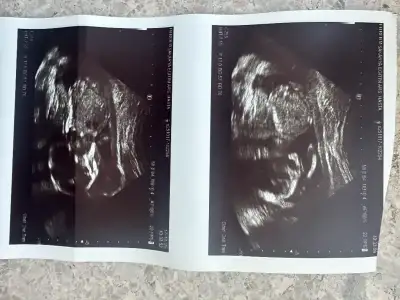

kizlar yüksek riskli çıkmış dediler cok gerginim suan hic bisey anlamadım acil amniyosentez diyolar anlıyormusunuz sonuclardan